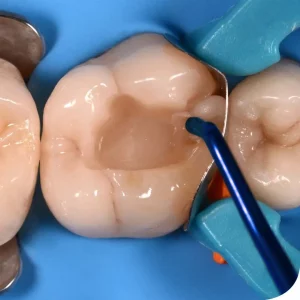

The GDC Conservative Kit Instruments Set of 19 in Pouch (CIP19) is a comprehensive set of dental instruments designed for conservative dental procedures such as fillings, extractions, and other restorative treatments. The kit includes 19 essential instruments made of high-quality stainless steel, all neatly arranged in a convenient pouch for easy storage and transport. This kit is ideal for dentists and dental professionals who want a reliable and complete set of instruments for conservative dental procedures. The instruments are designed for precision and durability, ensuring consistent and efficient performance during every procedure. The pouch also makes it easy to keep the instruments organized and within reach, making it a practical choice for both mobile and stationary dental clinics.